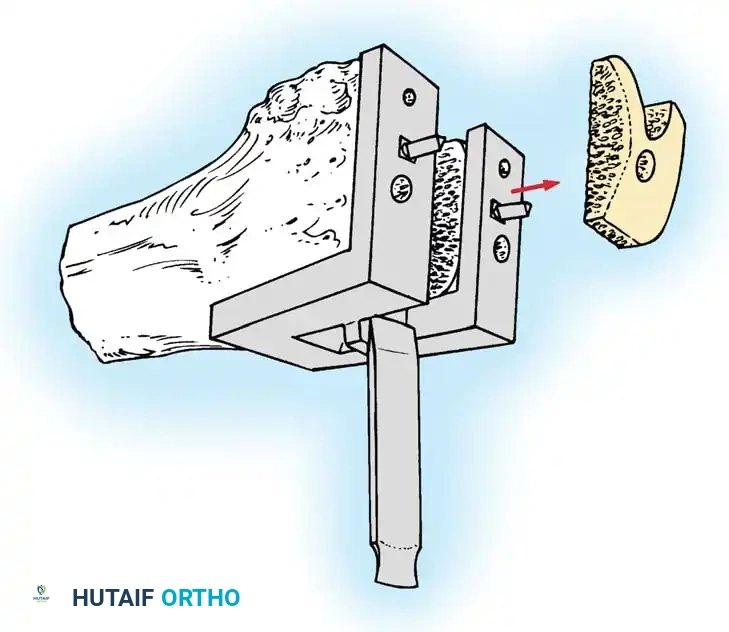

Proximal Tibial Preparation

The goal of the tibial resection is to create a flat, stable platform perpendicular to the mechanical axis of the tibia in the coronal plane, while recreating the appropriate posterior slope in the sagittal plane.

- Cut the tibia perpendicular to its mechanical axis. Extramedullary alignment guides are most commonly used, referencing the center of the tibial tubercle proximally and the center of the talus distally.